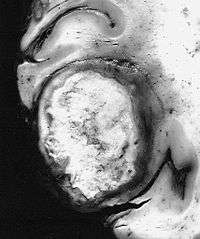

Some glioblastomas, such as this giant-cell variant, are discrete firm masses which clinically and radiographically simulate metastatic carcinoma | |